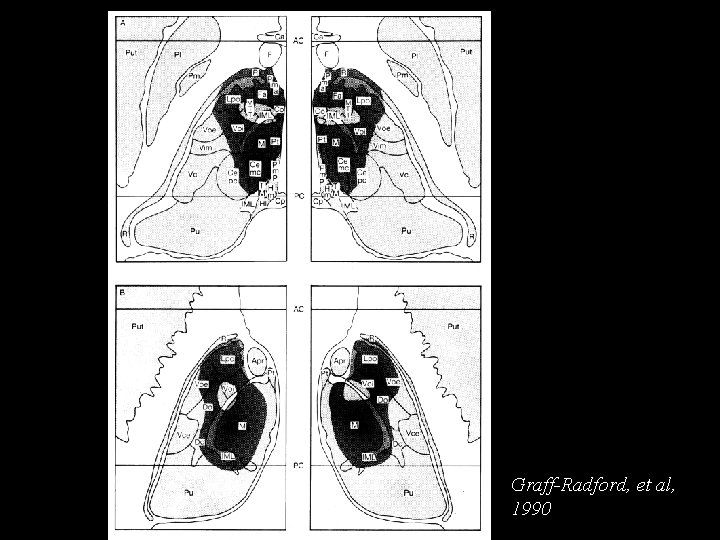

Graff-Radford, et al, 1990